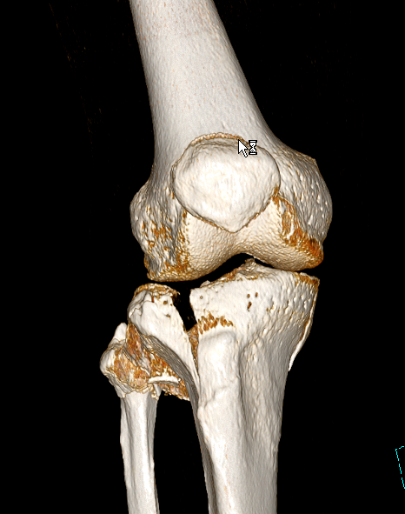

2、图3-6 术前CT见胫骨平台严重塌陷、劈裂

胫骨平台骨折的病人,如果在30年前大多数医院应该会选择保守治疗。那时CT尚未普及,而仅凭X片会低估其损伤的严重程度,容易产生可不必手术的假象,也难以准确判断骨折移位情况。即使想做手术,也没有什么好的内固定可供选用。

保守治疗肯定会遗留

膝关节功能障碍

、创伤性关节炎、跛行及畸形,造成残疾,而现在,我们采用积极的手术治疗让患者恢复了正常的外观及功能。